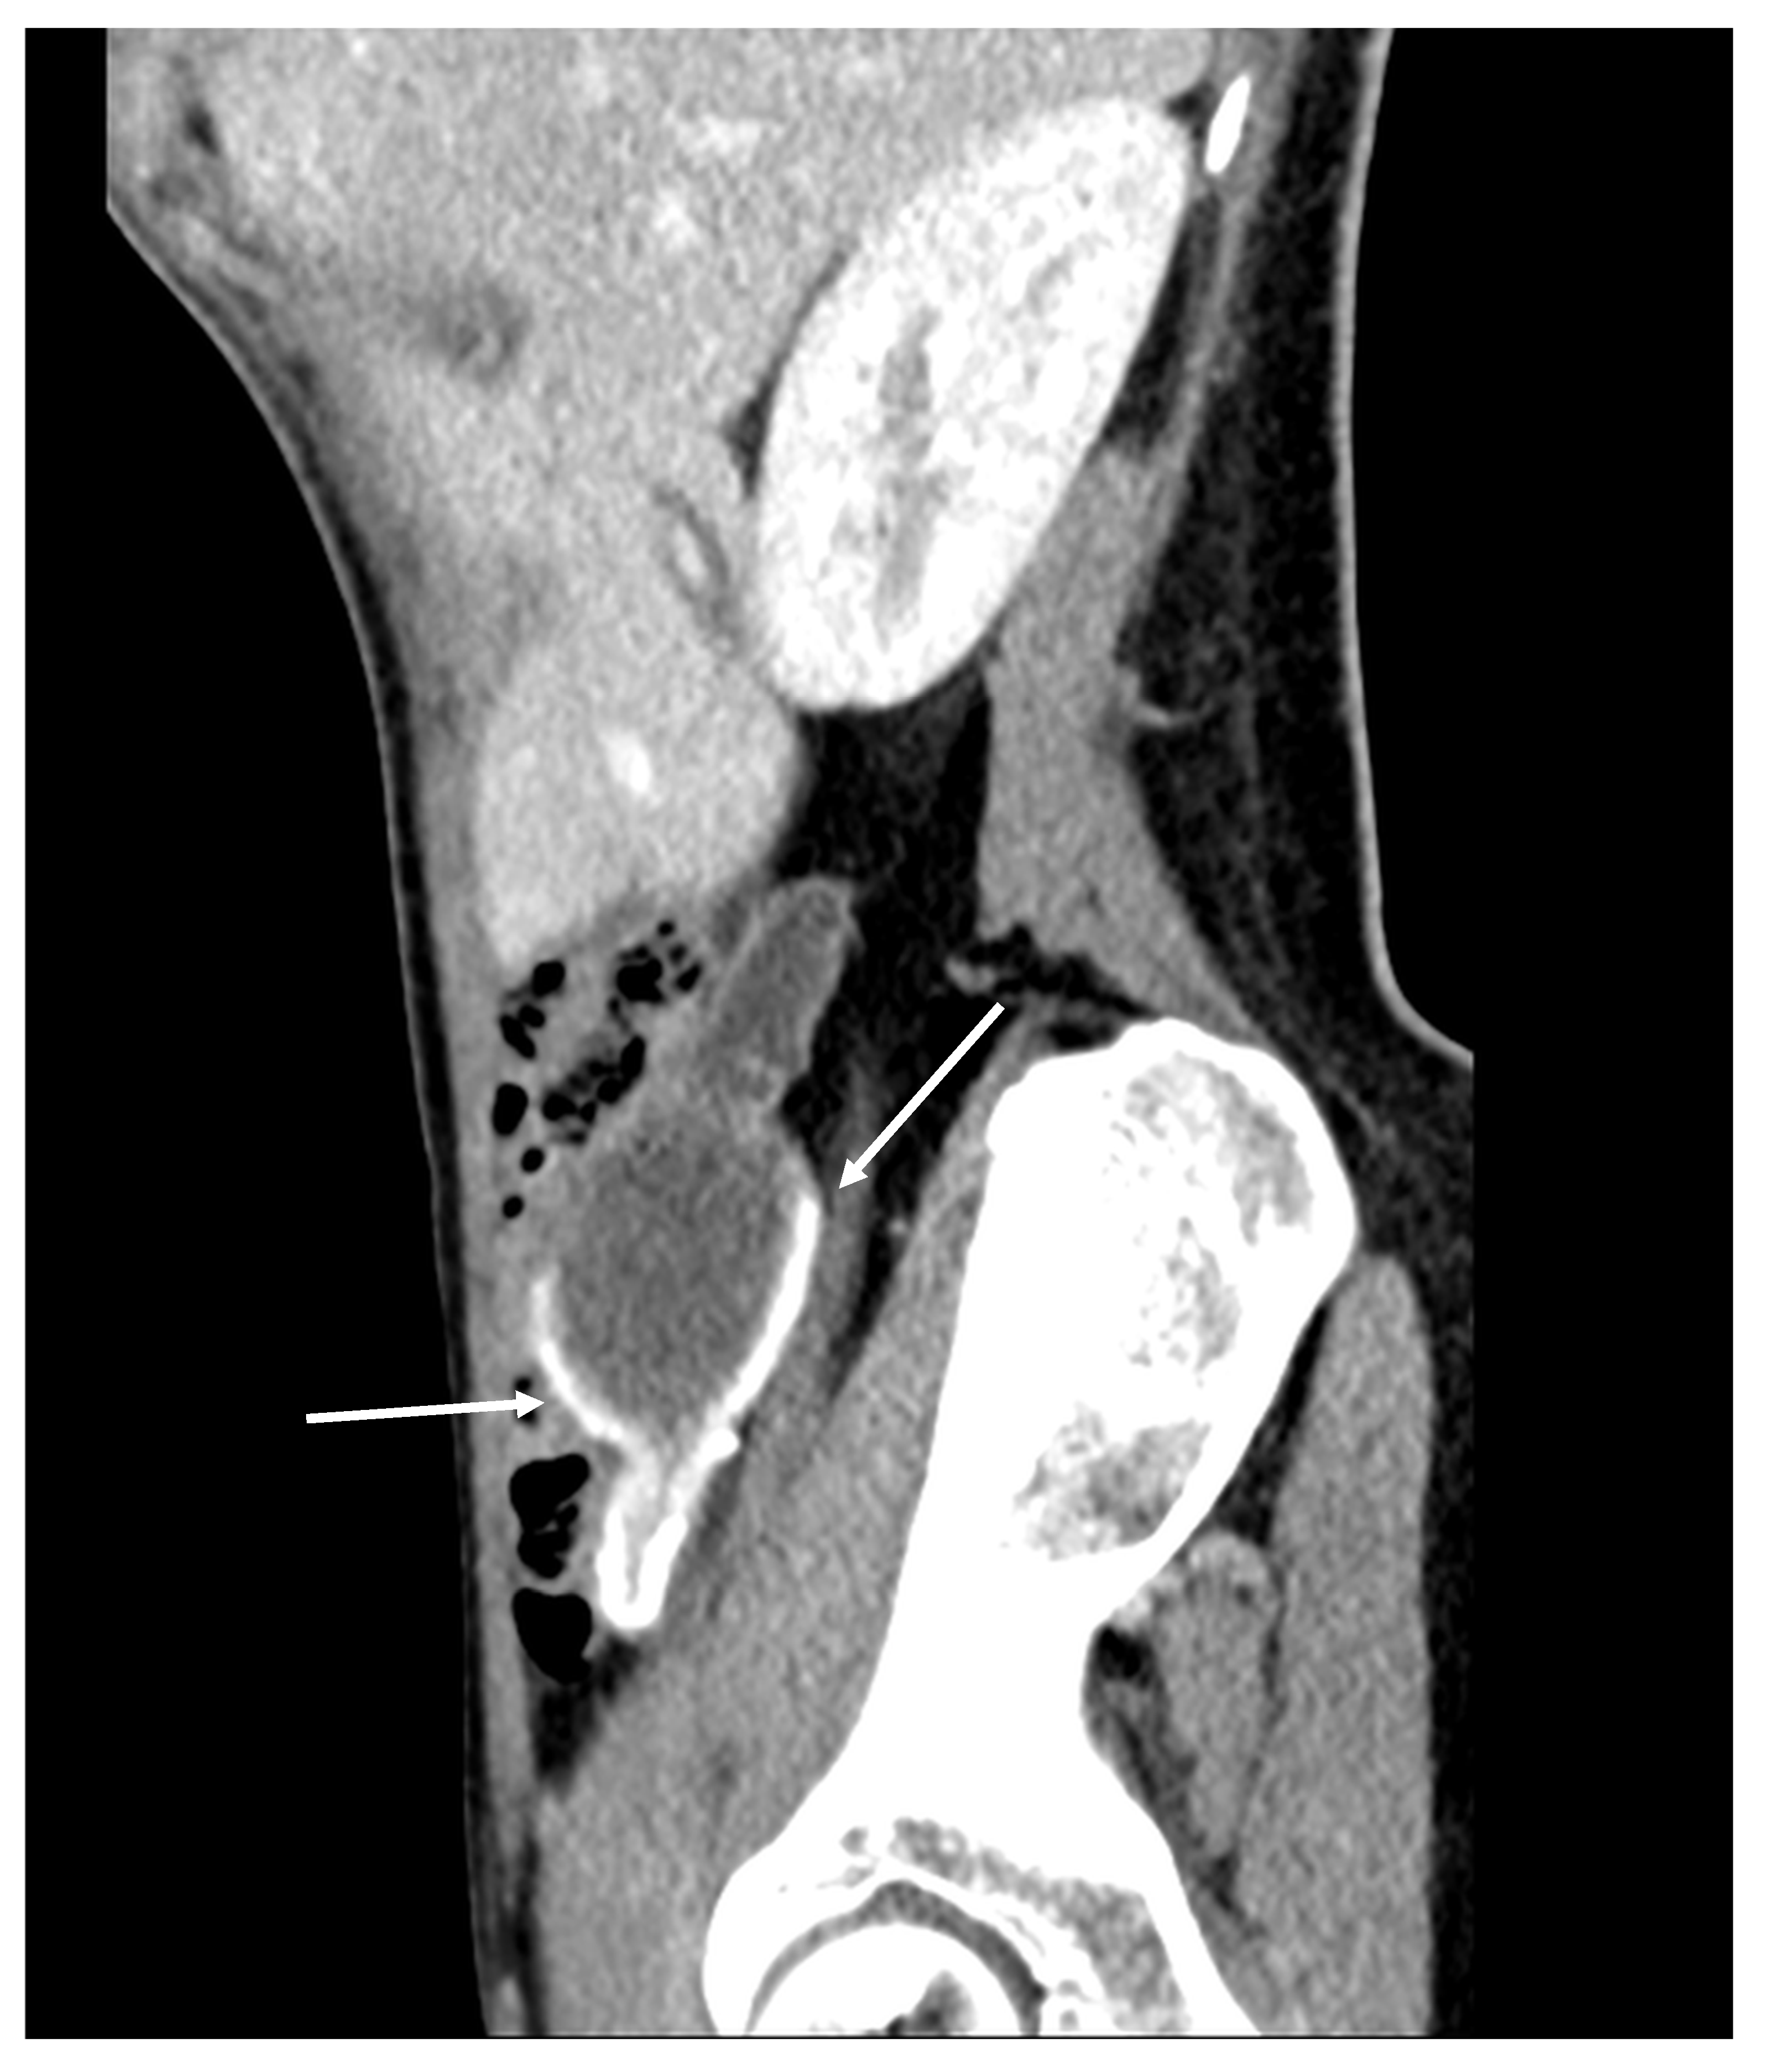

Figure 2. Mucocele of the appendix with calcification in the mucocele’s wall (arrows) (CT, venous phase, sagittal plane). Cystic dilatation of the appendix and calcification in the appendiceal wall. This is a typical sign for a mucocele, and it is present in 50% of patients [9].

Mucocele of the appendix refers to a dilated mucin-containing appendix. This term is mainly used by clinicians and radiologists (Figure 1, Figure 2, Figure 3 and Figure 4). It is necessary to distinguish “true mucocele” from a mucinous adenoid neoplasm [7]. The term mucocele was first used by Karl Freiherr von Rokitansky in 1842. Two years later, Werth used the term pseudomyxoma peritonei [4]. The clinical signs are minimal or often completely absent. The rupture of the mucocele can also be asymptomatic. Mucocele may be found on ultrasound or via a regular gynecological examination. A CT scan confirms the diagnosis. Treatment consists of the surgical removal of the dilated appendix, often together with the surrounding part of the cecum (Figure 5, Figure 6 and Figure 7). This approach is curative if there is no rupture or presence of tumor cells on the peritoneal surface. The diagnosis is confirmed through pathological examination of the specimen (Figure 8).